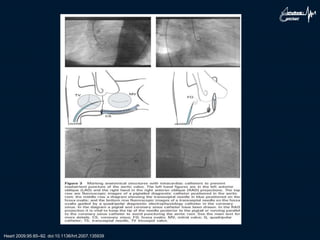

heart.bmj.com on 16 June 2009

TEE Guided: Tenting Atrial Septum